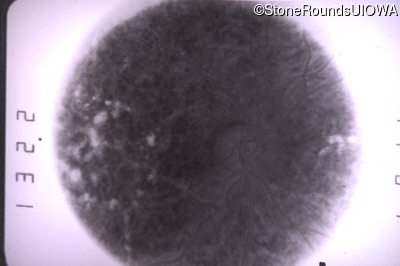

Fundus Photography - Left - 20/50 -2 sc

Exemplar